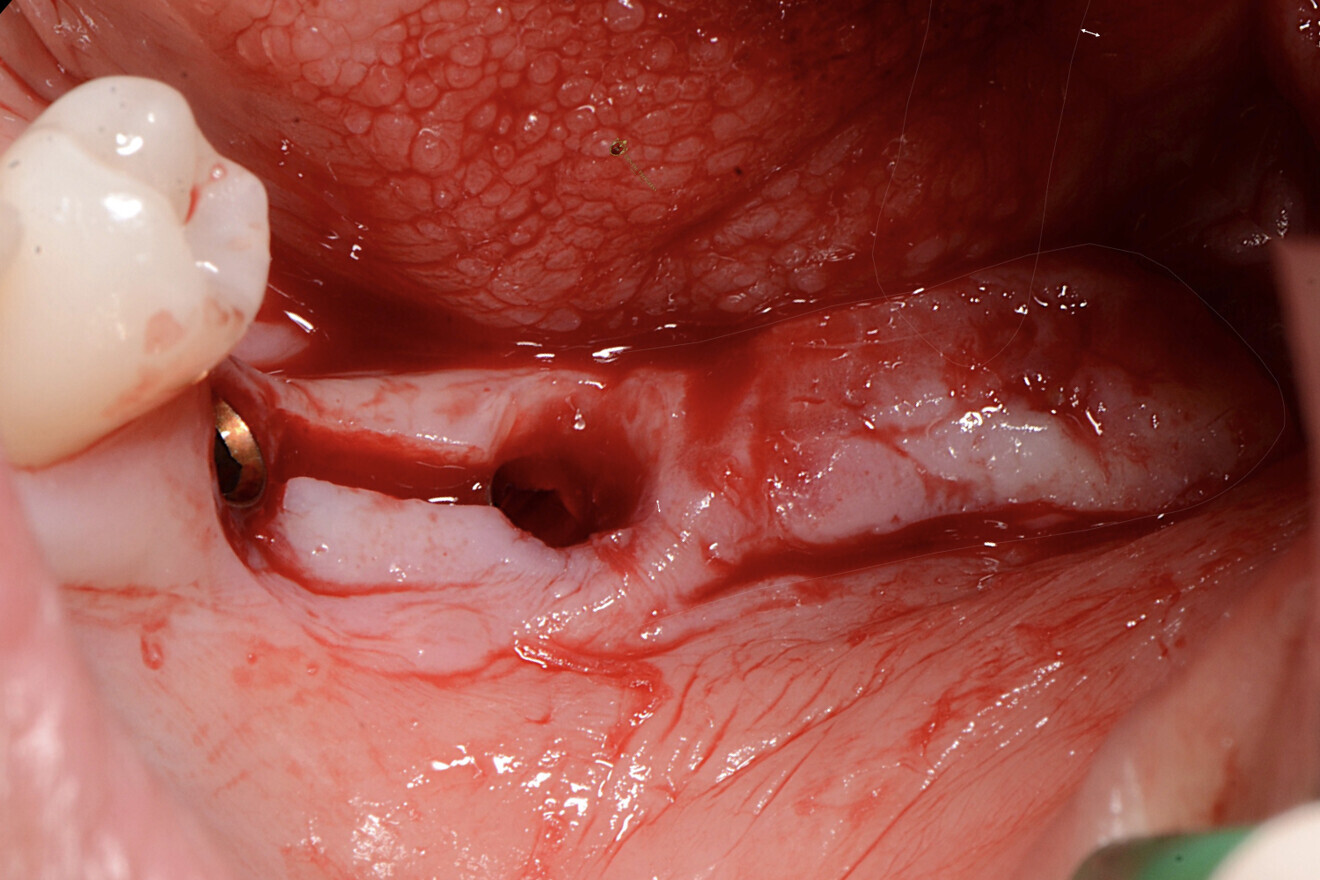

Fig. 1 : Situation préopératoire, montrant la zone concave entre les implants, favorisant la rétention de résidus alimentaires et la péri-implantite.

Le patient, 47 ans, présentait une résorption importante de la crête alvéolaire postérieure mandibulaire résultant de l’extraction des molaires (Fig. 1). Une récession gingivale péri-implantaire avec présence d’un tissu kératinisé minimal (moins de 1 mm) a été diagnostiquée au niveau de deux sites postérieurs. Le conditionnement des tissus mous péri-implantaires a été effectué quatre mois après la chirurgie implantaire.